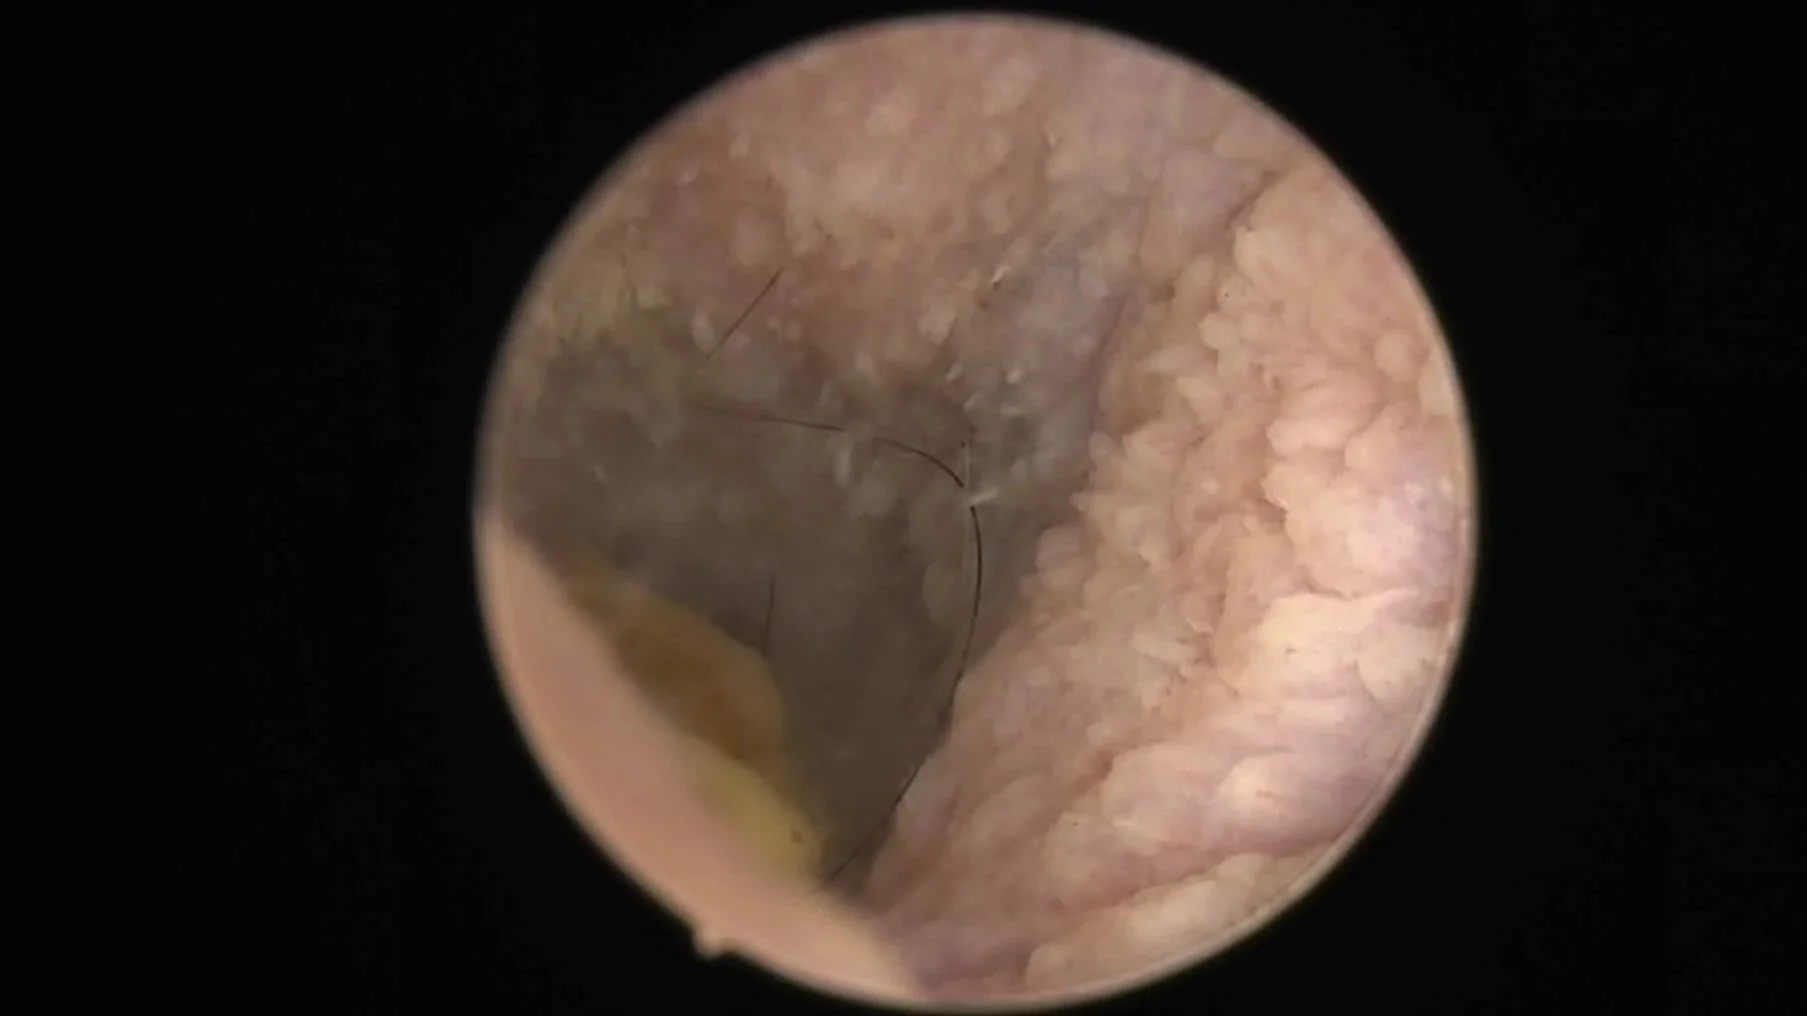

Chronic inflammatory changes of the vertical ear canal of a dog.

Chronic, recurrent or severe otitis externa is painful and frustrating (for your patient, their owner and you).

Often the first step towards resolution of chronic otitis externa is a thorough ear examination and deep ear clean under anaesthesia via video-otoscope. If there is significant canal stenosis, oral steroid medication is often prescribed for 1- 2 weeks to open up the ear canal prior to video-otoscopy.